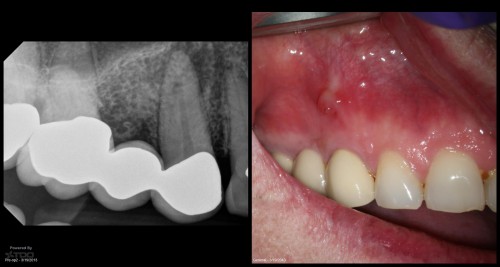

#13 – Caries Driven Access

– Sub-gingival caries distal to an isolated #13 – Gingivectomy and isolation done – Caries […]